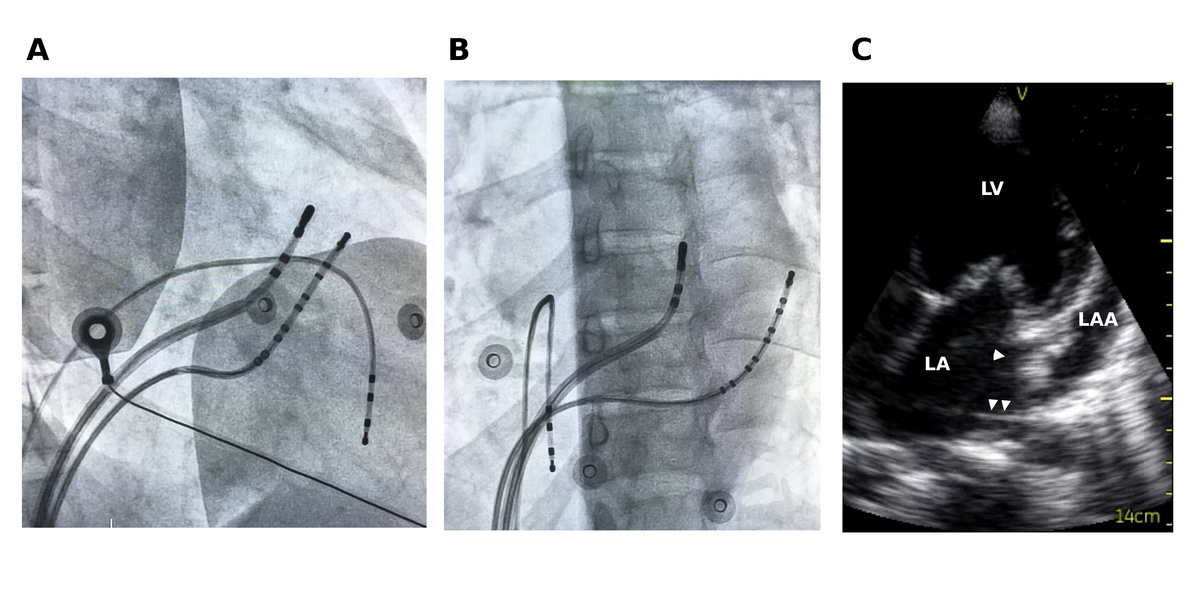

#10 Consider non annular location of AP

fig2.jpg

fig3.jpg